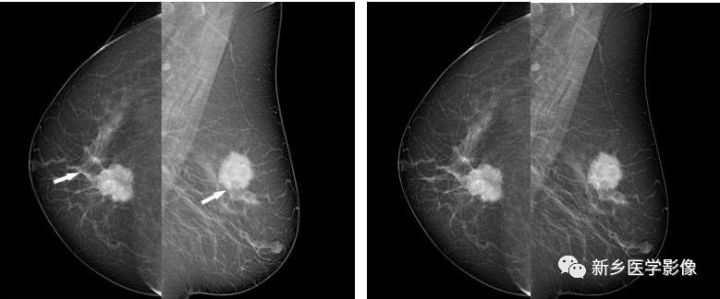

乳腺良性肿块X线图像

右乳CC位片示肿块圆形,边缘光滑、清晰,见透亮线环绕(白箭)

乳腺恶性肿块X线图像

a. 左乳CC位和b. MLO位片示肿块边缘分叶状,见数个长毛刺,周围血管增粗(白箭)